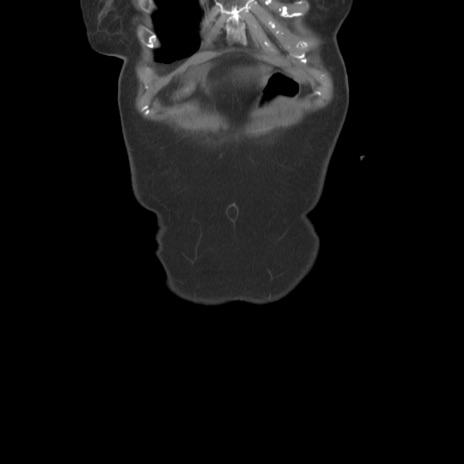

横断像

【症例】80歳代女性

【主訴】下腹部痛

【現病歴】約8時間前より下腹部痛の出現あり、救急外来受診。

【既往歴】両側付属器切除

【身体所見】意識清明、下腹部正中に手術痕あり、その部位に一致して圧痛と反跳痛あり。腸蠕動音は亢進。

【データ】WBC 9300、CRP 0.15